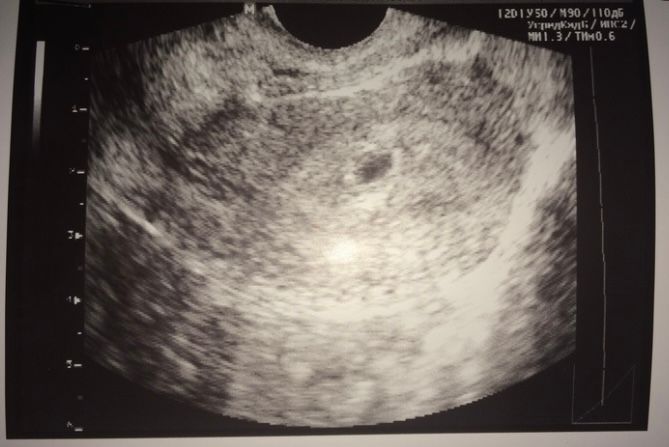

А во вторых, эмбрион пока еще не увидели, так как сказали срок маленький))

Но самое главное, что мы на нужном месте!))))

Нет, только желточный мешочек. ️ а сегодня в 7 увидели и сердце бьется...